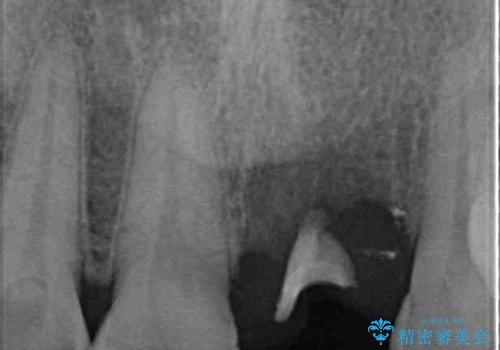

インプラント治療を希望されておりましたが、軟組織の欠損が非常に大きいため、骨の回復を待ちながら歯肉の形態を整えていくこととしました。

歯肉形態を概ね回復するタイミングでインプラントを埋入し、補綴治療を行うこととしました。

骨の前後幅が小さかったため、細いインプラントを選択せざるを得ない状況でした。咬合力が非常に強い方のため、就寝時のマウスピース装着を徹底していただき、インプラントへの負担を軽減することとしています。